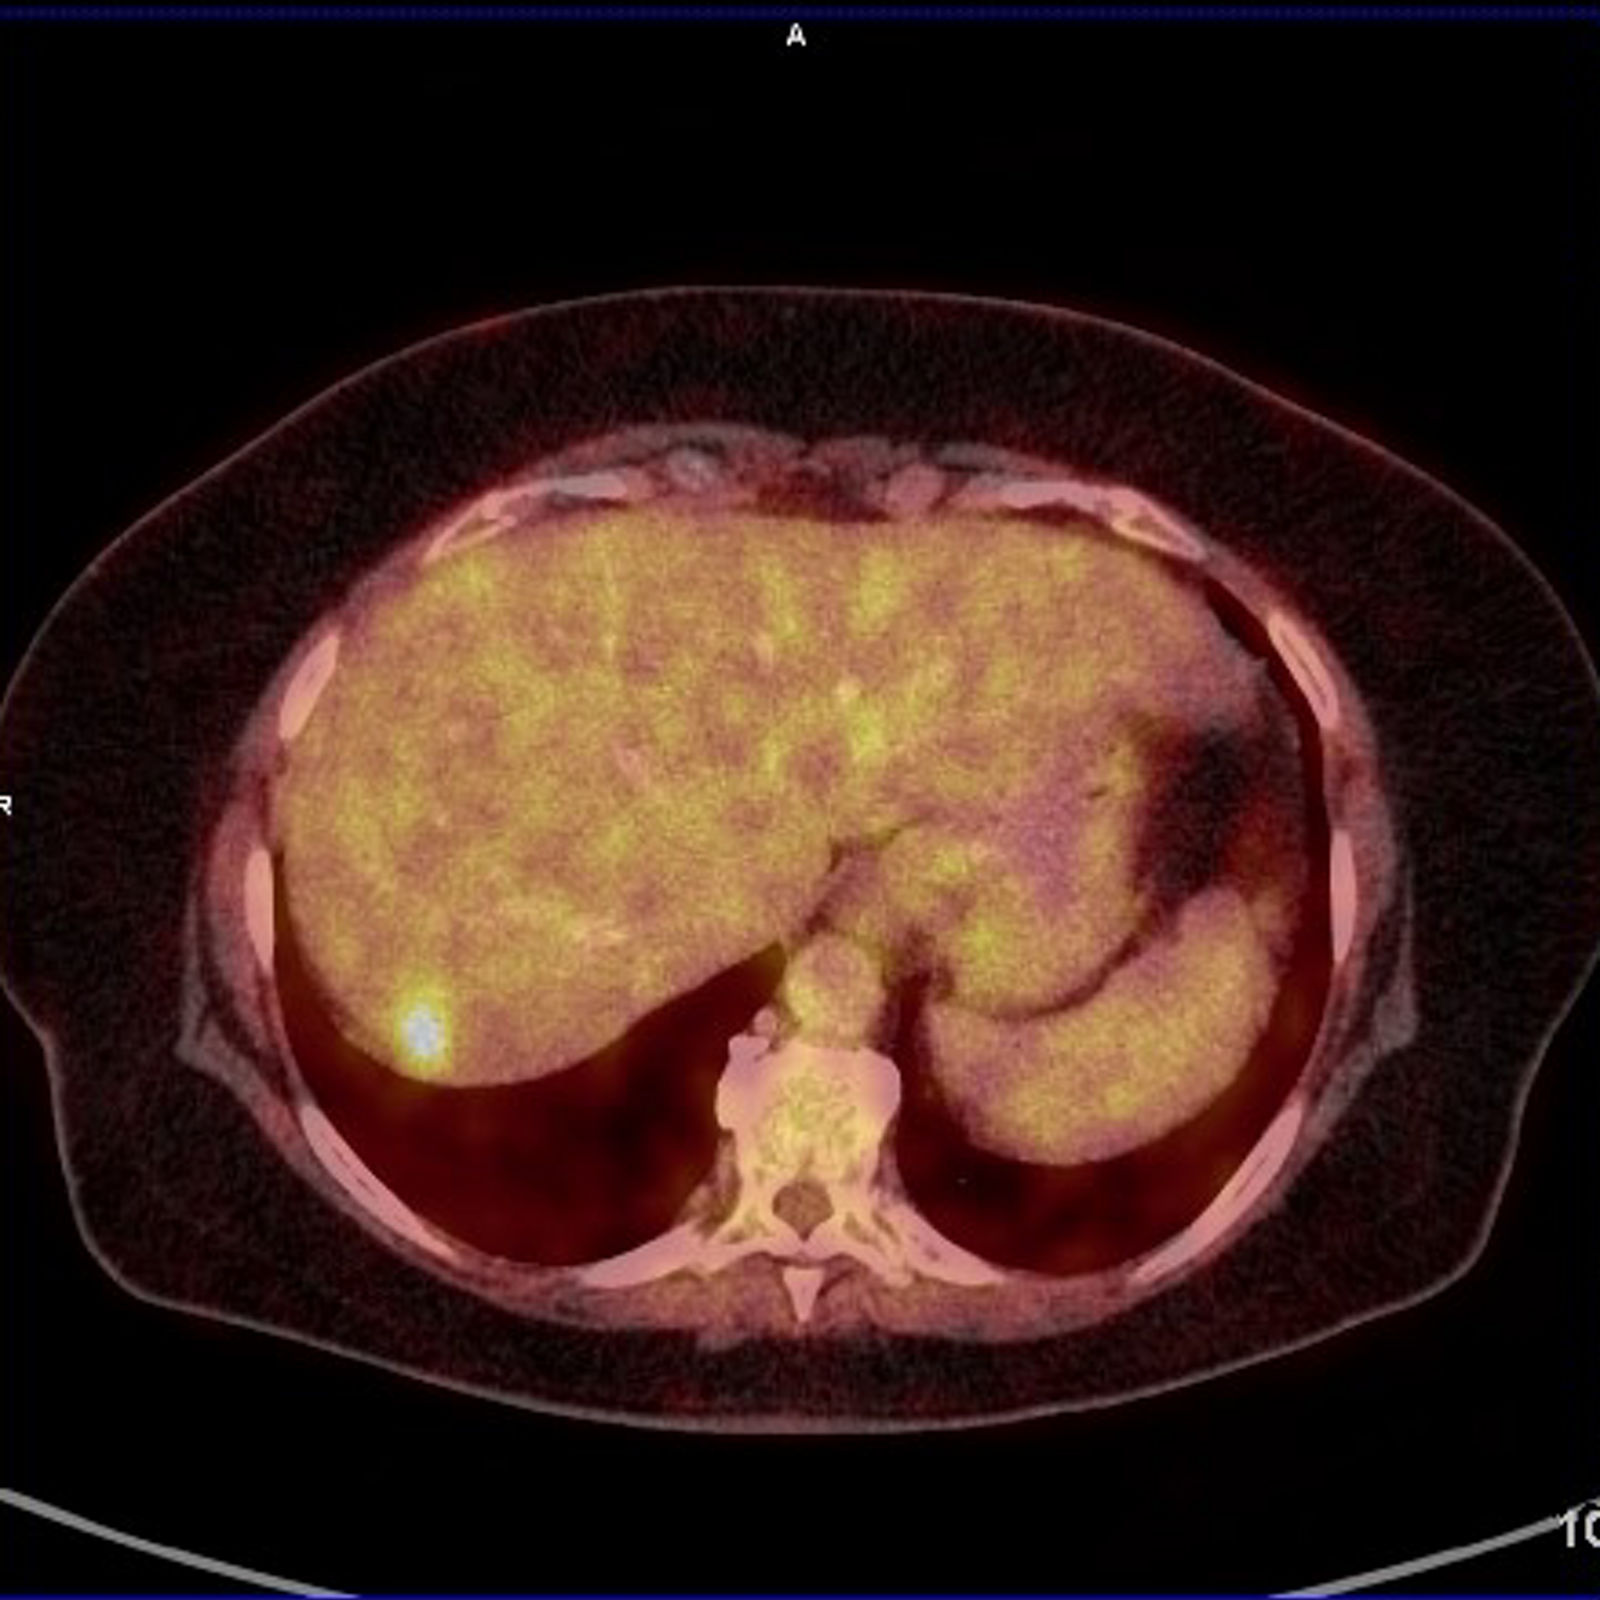

Die PET-CT-Untersuchung ist eine kombinierte nuklearmedizinisch-radiologische Bildgebung, eine Positronenemissionstomographie kombiniert mit Computertomographie. Sie stellt auf der einen Seite Stoffwechselveränderungen dar, auf der anderen Seite morphologische Veränderungen.

Meist wird mit F-18 markierte Glukose verwendet, um die Verteilung des Glukosestoffwechsels darzustellen, es können aber auch z.B. Rezeptor gerichtete Substanzen verwendet werden. Im CT-Teil der Untersuchung werden die morphologischen Verhältnisse dargestellt, je nach Fragestellung und Vorbefunden mit diagnostischer CT oder als Niedrig-Dosis-CT.

Kolorektale Karzinome haben in der Regel einen deutlich gesteigerten Glukosestoffwechsel, d.h. sie können in der PET-CT durch eine vermehrte Speicherung des verwendeten Radiopharmakons nachgewiesen werden. Auch Metastasen eines kolorektalen Karzinoms weisen diesen erhöhten Glukosestoffwechsel auf.

In der Beurteilung möglicher Fernmetastasen kann die PET-CT wertvolle Zusatzinformationen liefern, die die primäre Therapie beeinflussen können, z.B. bei der Beurteilung von Lungenrundherden unklarer Dignität, die Lungenmetastasen entsprechen oder aber auch Zweitmalignomen oder narbigen Veränderungen entsprechen könnten.

Auch kann vor Resektion von resektablen Lebermetastasen die PET-CT mit dem Ziel der Vermeidung einer unnötigen Laparotomie durchgeführt werden. (S3-Leitlinie Kolorektales Karzinom)